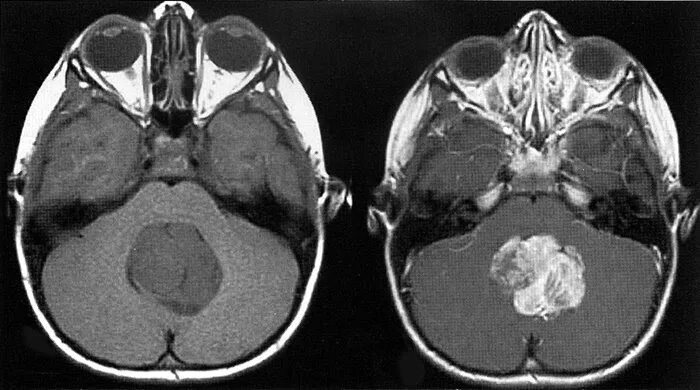

Медуллобластома это